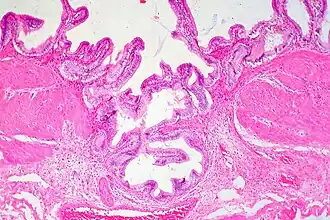

Gallbladder adenomyomatosis is a benign disease of the gallbladder characterized by hyperplasia of the mucosal epithelium and smooth muscle cells inside the muscularis propria.[4][5][6] The excessive proliferation of epithelial cells causes the mucosa to invaginate into the muscular layer lining the gallbladder wall, resulting in characteristic diverticula known as Rokitansky-Aschoff sinuses. These sinuses may be filled with biliary sludge, cholesterol crystals, or gallstones.[4][5][6]

There are three morphologic variants described in the literature – diffuse, segmental, and localized.[5][6] Diffuse, also known as generalized, adenomyomatosis has a widespread distribution of hyperplastic changes and thickening across the gallbladder wall.[5][6] The localized form of adenomyomatosis is also known as a gallbladder adenomyoma (in a similar manner that uterine adenomyoma is the localized variant of adenomyosis). The localized form is a single mass, typically in the fundus, that protrudes into the lumen of the gallbladder in the form of a polyp.[5][6] The segmental form is characterized by its annular (ring-shaped) distribution of adenomyomatosis in the body of the gallbladder, often giving it an hourglass-like appearance.[5][6]

Ultrasound is the preferred initial diagnostic choice for suspected gallbladder disease. Several distinct features of adenomyomatosis are discernable using ultrasound, making it a reliable modality for diagnosis.[4][5][6] The most characteristic features seen on ultrasound are the Rokitansky-Aschoff sinuses, which present either as echogenic foci when filled with biliary sludge/gallstones or anechogenic foci when filled with normal bile.[4][5][6] Other key features that may be seen include wall thickening and ring-down artifacts known as "comet tails" (produced by reverberations of sound between the sinuses).[4][5][6] Ultrasound can also distinguish between diffuse, segmental, and localized variants of adenomyomatosis based on morphology.[5][6]

In some cases, gallbladder wall thickening may be seen on ultrasound but is poorly defined and lacking specificity, particularly if the characteristic Rokitansky-Aschoff sinuses are not visualized. This can make it difficult to distinguish adenomyomatosis from other conditions that result in gallbladder wall thickening such as gallbladder cancer.[4][5][6] In these cases, MRI can prove helpful in providing the resolution needed for diagnosis. Especially effective is the T2-weighted MRI at visualizing the pathognomonic Rokitansky-Aschoff sinuses, which appear as round-shaped hyperintense cystic spaces that align in a curvilinear fashion along the gallbladder wall in a pattern described as the ”pearl necklace sign”.[4][5][6]